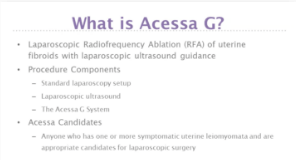

The Acessa procedure is a less invasive treatment option for women with symptomatic uterine fibroids.

The Acessa procedure offers optimized technology for more complete fibroid treatment, provides relief with low reintervention, and allows you to care for more patients by offering more uterine sparing options. Using controlled radiofrequency energy (heat), the Acessa procedure causes coagulative necrosis of the fibroid tissue. The treated tissue softens and shrinks over time, allowing fibroid symptoms to resolve without difficult and time-consuming uterine suturing.1

IMPORTANT SAFETY INFORMATION

The Acessa ProVu system is indicated for use in percutaneous, laparoscopic coagulation and ablation of soft tissue, including treatment of symptomatic uterine fibroids under laparoscopic ultrasound guidance. The Acessa ProVu system is contraindicated for patients who are not candidates for laparoscopic surgery and/or patients with a uterus adherent to pelvic tissue or viscera. The Acessa ProVu system’s guidance system is not intended for diagnostic use. Please read all instructions for use of the Acessa ProVu system prior to its use. Safe and effective electrosurgery is dependent not only on equipment design but also on factors under control of the operator. Rare but serious risks include, but are not limited to, infection, injury to adjacent structures, blood loss and complications related to laparoscopy and/or general anesthesia. Insufficient data exists on which to evaluate the safety and effectiveness of the Acessa ProVu system in women who plan future pregnancy, therefore the Acessa ProVu system is not recommended for women who are planning future pregnancy.